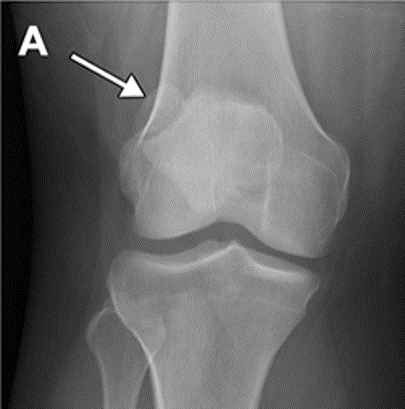

7

Q

Knee: Osteochondritis dissecans

PE and test

A

Physical Exam:

Localize joint line tenderness

Occasionally will have effusion

Occasionally will have popping

Tests: start with X-Rays (knee – notch view) but MRI is needed to determine severity

8

Tx and pearls

Treatment:

Kids: more conservative tx like rest, cast, NWB x several months

Adults: stable – weight bearing restrictions, unstable surgical repair – drilling, screw fixation, resurfacing, joint replacement

Both require surgical removal if there is a loose body in the joint

Pearls:

Most common location of OCD in the knee is the posterior lateral aspect of the medial femoral condyle (70%), capitellum of humerus, talus